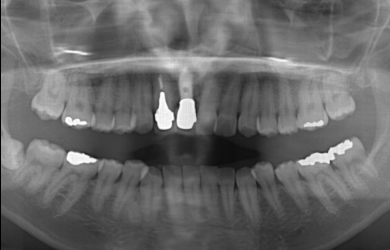

| 治療方針 | 抜歯した部分の骨が薄いため、そのままではインプラントを埋入出来ないため、GBR法と併用して、自分の骨を薄い部分に移植し、骨のボリュームを確保し、且つインプラント手術を同時に行うことにより、患者様にかかる外科的負担を軽減、治療期間を短縮する。 |

| 治療内容 | インプラント1本(GBR+自家骨移植)、メタルボンドセラミック2本 | ||||||||||||||||||||||||||||||||

| 治療期間 | 6ヶ月 |